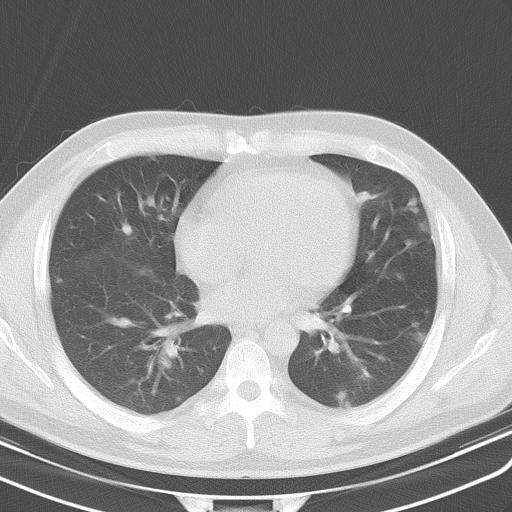

患者男性 35 主因发热咳嗽四天,血象不高,心肺听诊未见异常,无其它病史及传染病接触史。

双肺多发结节,部分边缘不清,示磨玻璃样,分布支气管血管走形 考虑:血源性肺脓肿,炎性肉芽肿(韦格肉芽肿)霉菌感染 结节病 转移瘤不除外

年轻,病史短,症状相对轻,肺内多发腺泡结节,多呈ggo,上纵隔淋巴结大考虑:1肺内淋巴瘤2非典型病源体感染性疾病3肿瘤播散

两肺多发结节,部分病灶边缘不清,且示毛玻璃影。分布特点为沿血管支气管分布。考虑如下:

1.双肺门及纵隔淋巴结肿大,双肺多发结节,结节病

2.hiv感染,年龄不大,无原发肿瘤病史,建议查hiv。

3.转移瘤,边缘毛糙,无钙化,来源于消化系统。